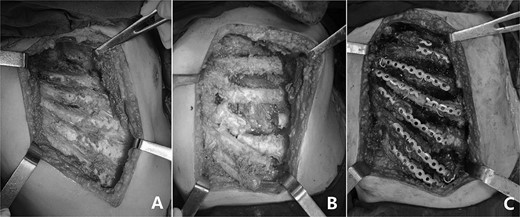

The patient is a 35-year-old male from western China. He suffered from pleuritis at the age of 17. Due to the incomplete treatment at that time, the pleuritis turned into empyema later. At the early stage, his chest wall was not deformed. From the age of 25, his right chest wall began to be depressed and scoliosis gradually appeared. During this period, he did not receive any effective treatment, and his condition gradually worsened. In half a year before admission, the patient often felt dyspnea, so he was admitted to our hospital for surgical treatment. The preoperative physical examination showed that the patient’s chest was asymmetric, the right side was largely depressed (Fig. 1A), the breath sound was low and the spine was scoliosis. Imaging examination showed that the right chest wall was depressed and shrunk, there were obvious lesions in the right thoracic cavity and the pleura was thickened (Fig. 1B and C). The patient was diagnosed as right empyema with right chest wall depression and scoliosis before operation. After full preparation, his operation was performed under general anesthesia. Left lateral decubitus position was adopted, and the right subaxillary longitudinal incision was performed. Subcutaneous and muscular tissues were dissected to expose the right ribs (Fig. 2A). After the ribs were cut in crisscross way, the thickened pleura was exposed (Fig. 2B). The pleura is stripped, and all lesions in the thoracic cavity were cleared. The thoracic cavity and surgical field were washed repeatedly, and then the chest wall was reconstructed with MatrixRIB. Firstly, the two ends of the cut rib were stretched as far as possible, and then MatrixRIB was used to extend and fix the two ends (Fig. 2C). Thoracic cavity and surgical field were washed again. After drainage tubes were retained, the incision was closed and the operation was completed (Fig. 3). There were no complications during the operation and the postoperative recovery was satisfactory. After operation, the right chest wall depression was basically eliminated, the chest wall was symmetrical on both sides and scoliosis was significantly reduced. The drainage tubes were pulled out 8 days after the operation. The incision healed well and the suture was removed 14 days after the operation. He was discharged 15 days postoperatively without any complaint.

(A) The depressed ribs were exposed; (B) The ribs were cut in crisscross way and (C) The deformity was corrected with MatrixRIB.